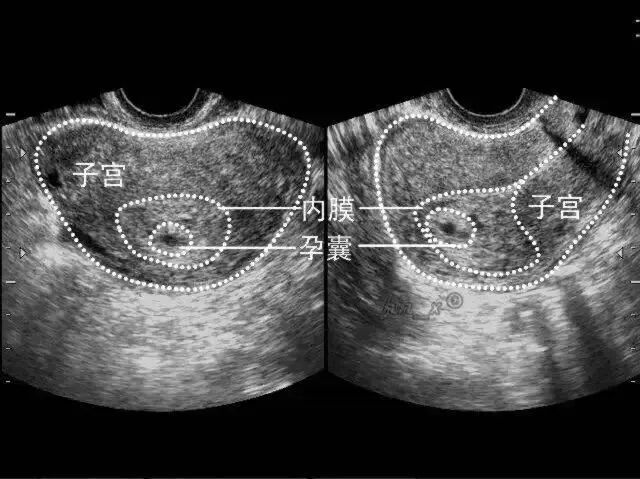

②B超:宫腔内只有孕囊而无胎芽组织的异常妊娠,孕囊直径>20mm,而囊内仍未见到胚芽,提示空囊。

如果孕60天左右,只有孕囊,没有胚芽和卵黄囊及胎心搏动,基本就是空囊了。

空囊一般轮廓不规则或有缺损,常小于孕龄呈空虚状况,张力差。

空囊由于胚胎死亡或枯萎,可位于宫腔中央或偏向一侧,一般下移至子宫颈内或宫腔下段;空囊随孕龄不生长或生长缓慢。